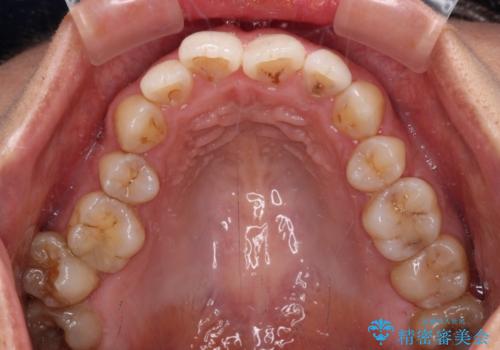

前歯のデコボコを改善 インビザラインの矯正治療

- 前歯のデコボコを治したいとのことで来院された患者様です。

上下顎ともに歯列全体の後方移動とIPR(歯と歯の間を削る)によってデコボコが解消するように設計し、インビザラインにより治療を行うこととしました。